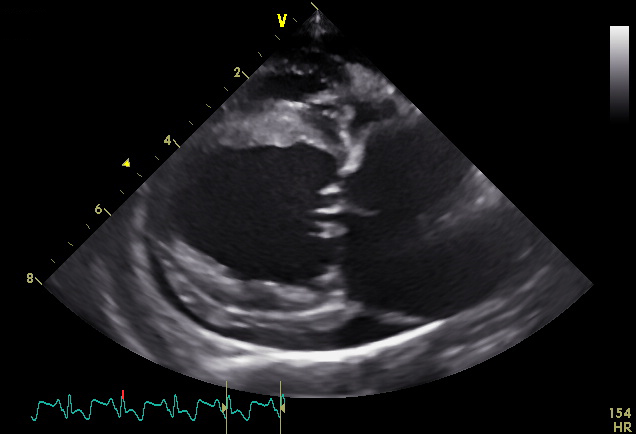

Bij cardiologische patiënten worden auscultatie, elektrocardiografie, Holter-monitoring (24u ECG) en echocardiografie met Doppler door ons uitgevoerd. Daarnaast wordt ook onderzoek verricht naar oorzaak, diagnose en therapie van congenitale en verworven hartaandoeningen bij honden, katten en andere diersoorten.